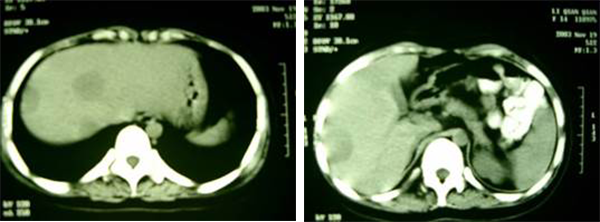

图1 位于肝右的叶肝母细胞瘤, 6个月,男婴

(1)CT表现

1)平扫:可见肝实性肿块,多由数个结节聚合成大块状,其边缘为高或等密度,中心呈低密度或高低不等密度。

2)增强扫描:在动脉期增强可见多个结节状增强染色征象,门静脉期肿瘤呈低密度,中心有不规则更低密度区域,为肿瘤坏死所致。有的肿瘤内含类似骨组织成分,CT 可显示钙化灶。CT平扫示右肝可见巨块状低密度占位性病变,边缘比较光滑,密度不均,内部可见不规则更低密度区域,其内斑点状钙化。增强示肿瘤可见增强,门静脉期肿瘤呈低密度,中心坏死无增强,肝内胆管扩张。

图2:肝右叶肝母细胞瘤的CT表现, 6个月男婴